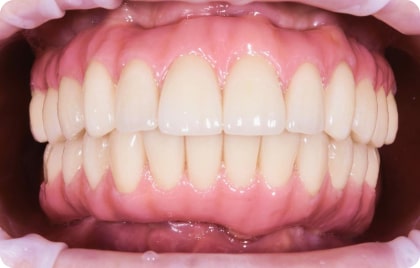

Зубы за 1 день за 5776р. в месяц

с пожизненной гарантией

По уникальной методике

БЕЗ отёков и надрезов